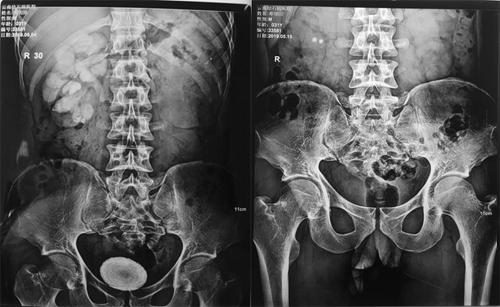

术前术后对比图

“膀胱结石治疗不及时危害极大,不但会引发炎症、梗阻性病变,导致肾功能受损,甚至可能导致尿毒症。结石长期慢性刺激膀胱壁,还可能导致癌变。”邓先生的主治医生、云南结石病医院泌尿外科学术带头人黄丽娟博士表示,“检查结果显示,邓先生患有‘膀胱结石、双肾重度积水、双肾功能重度受损’。其肾功能严重受损的主要原因是膀胱结石导致的尿路梗阻,引发肾积水所致。”